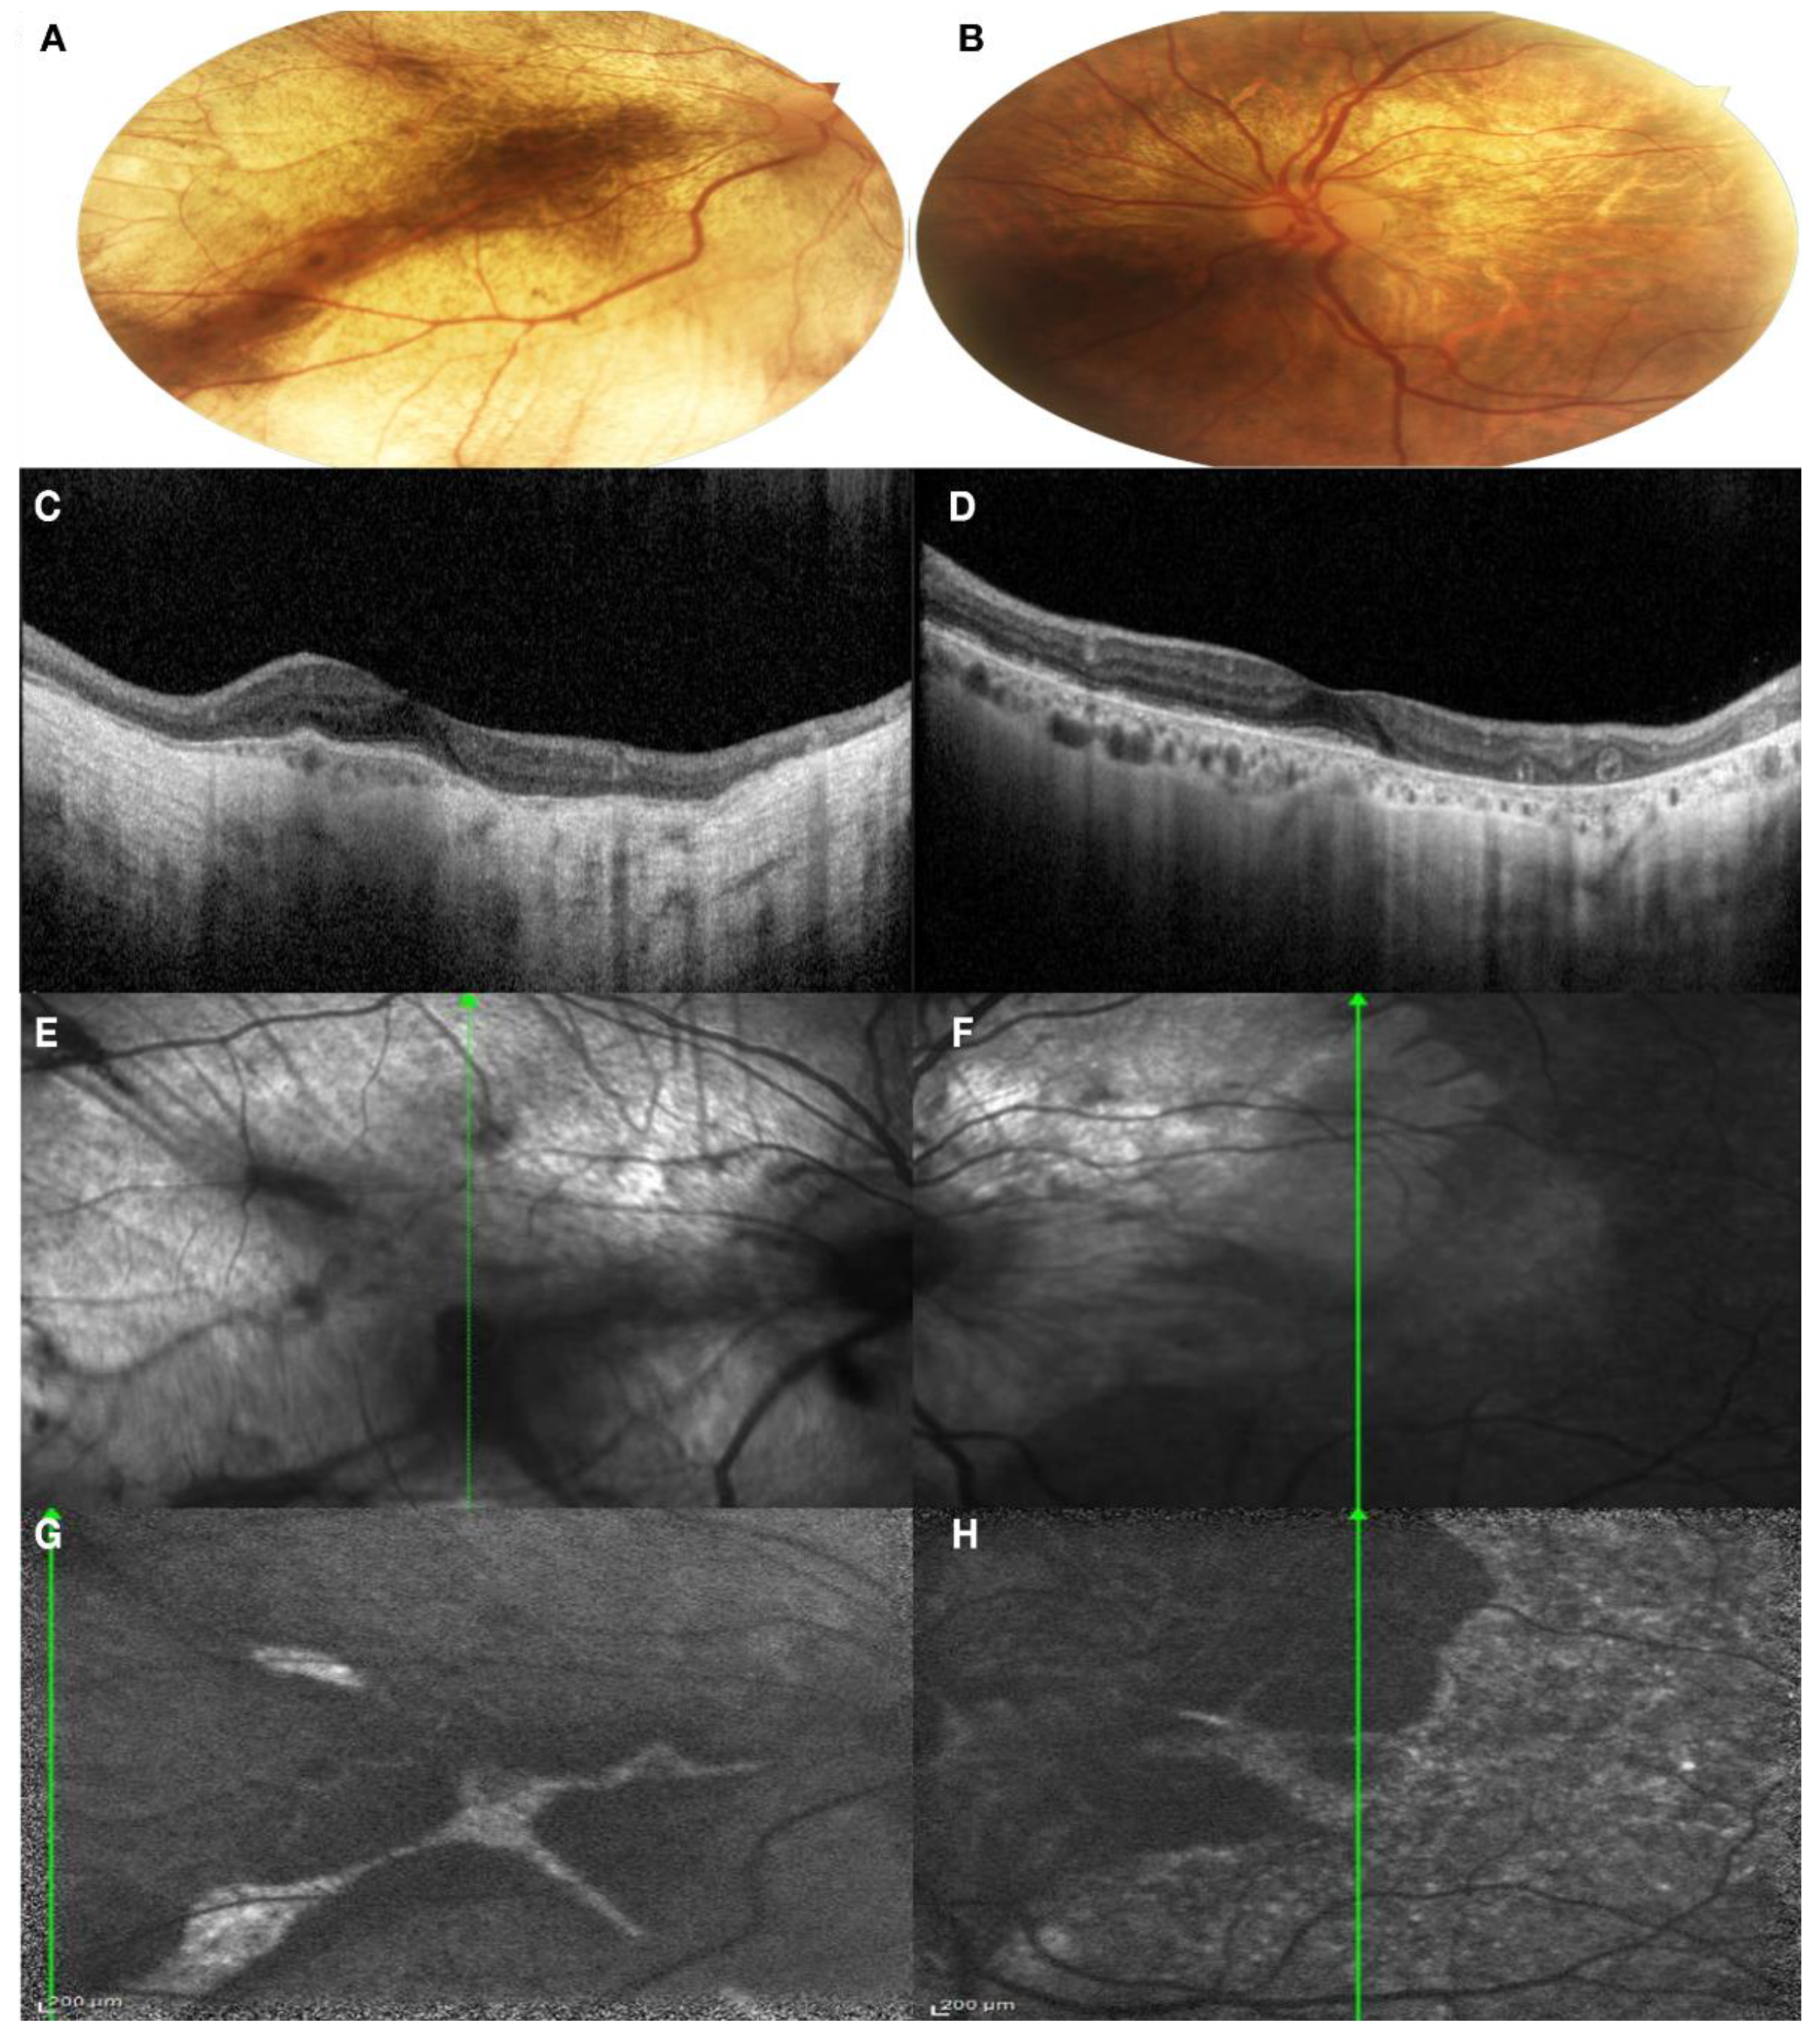

Patient II:2. The patient has mild myopia and her BCVA was 1.00 in both eye. No color vision defect was detected with the Ishihara test. Anterior segment examination was normal. On fundus examination, mild peripapillary atrophy was found, with areas of hyper-pigmentation in the perifoveal area. At the level of the vascular arcades, pigmentary changes were present, associated with areas of hyper-reflectivity. Macula seemed preserved (Figure 5A,B). On SD-OCT, the retinal profile was regular, with preservation of the physiological foveal depression. The inner retinal layer was preserved, but the Outer Nuclear Layer (ONL) and the Photoreceptor Layer were thinned in the perimacular zone. The Ellipsoid Zone (EZ) and the Interdigitation Zone (IZ) were irregular throughout all the macular and perimacular area. Even the RPE–Bruch’s membrane complex looked irregular, with small focal thickening points. Spots of hyper-transmission posterior to the RPE–Bruch’s membrane complex were present (Figure 5C,D). IR images revealed a normal aspect of the macular area and hypo-reflective areas among the vascular arcades and the mild periphery and focal hyper-reflective spot, corresponding to the focal thickening of the RPE (Figure 5E,F). FAF images showed a coarse pattern, with normal autofluorescence of the macular area and a generalized hypo-fluorescence of the vascular arcade area (Figure 5G,H).

Figure 5. Multimodal imaging of both eyes of Patient II:2. (A,B) Color fundus photography of both eyes showed mild peripapillary atrophy, areas of hyper-pigmentation in the perifoveal area and pigmentary changes at the level of the vascular arcades; (C,D) SD-OCT of both eyes showed thinning of the ONL in the perimacular zone. IZ-EZ and the RPE–Bruch’s complex were irregular, with spot of hyper-transmission posterior to the RPE-Bruch’s membrane; (E,F) IR images showed normal aspect of the macular area and hypo-reflective areas among the vascular arcades; (G,H) normal autofluorescence of the macular area and a generalized hypo-fluorescence of the vascular arcade area. (A,C,E,G): right eye; (B,D,F,H): left eye.